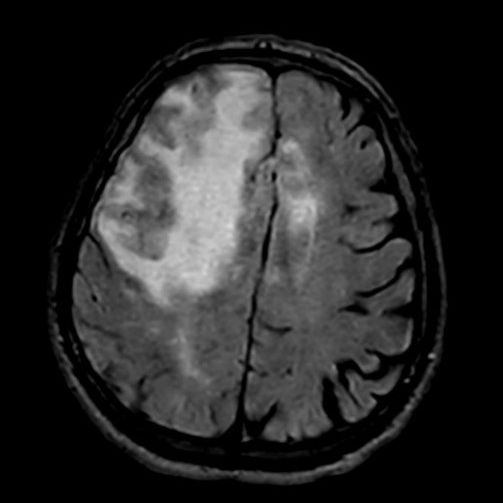

- A) Aksiyel planda FLAIR sekansta asimetrik kortiko-subkortikal vazojenik ödemi düşündüren yüksek sinyalli hafif ekspansil lezyonlar (turuncu ok).

- Difüzyon kısıtlılığının olmaması, leptomeningeal kontrastlanma, FDG-PET’te düşük aktivite, GRE sekansta yaygın hemosiderin kalıntılarının eşlik etmesi ile karakterizedir.

- 40 yaş üzeri bilinç bozukluğu, davranış değişikliği, fokal nörolojik bulgular, bulguların akut intrakraniyal kanama ile doğrudan ilişkilendirilmemesi, subkortikal beyaz cevhere uzanan asimetrik unifokal ya da multifokal kortiko-subkortikal ödemli lezyonlara serebral mikro/makrokanama, superfisiyal siderozisin eşlik etmesi halinde mutlaka düşünülmelidir.